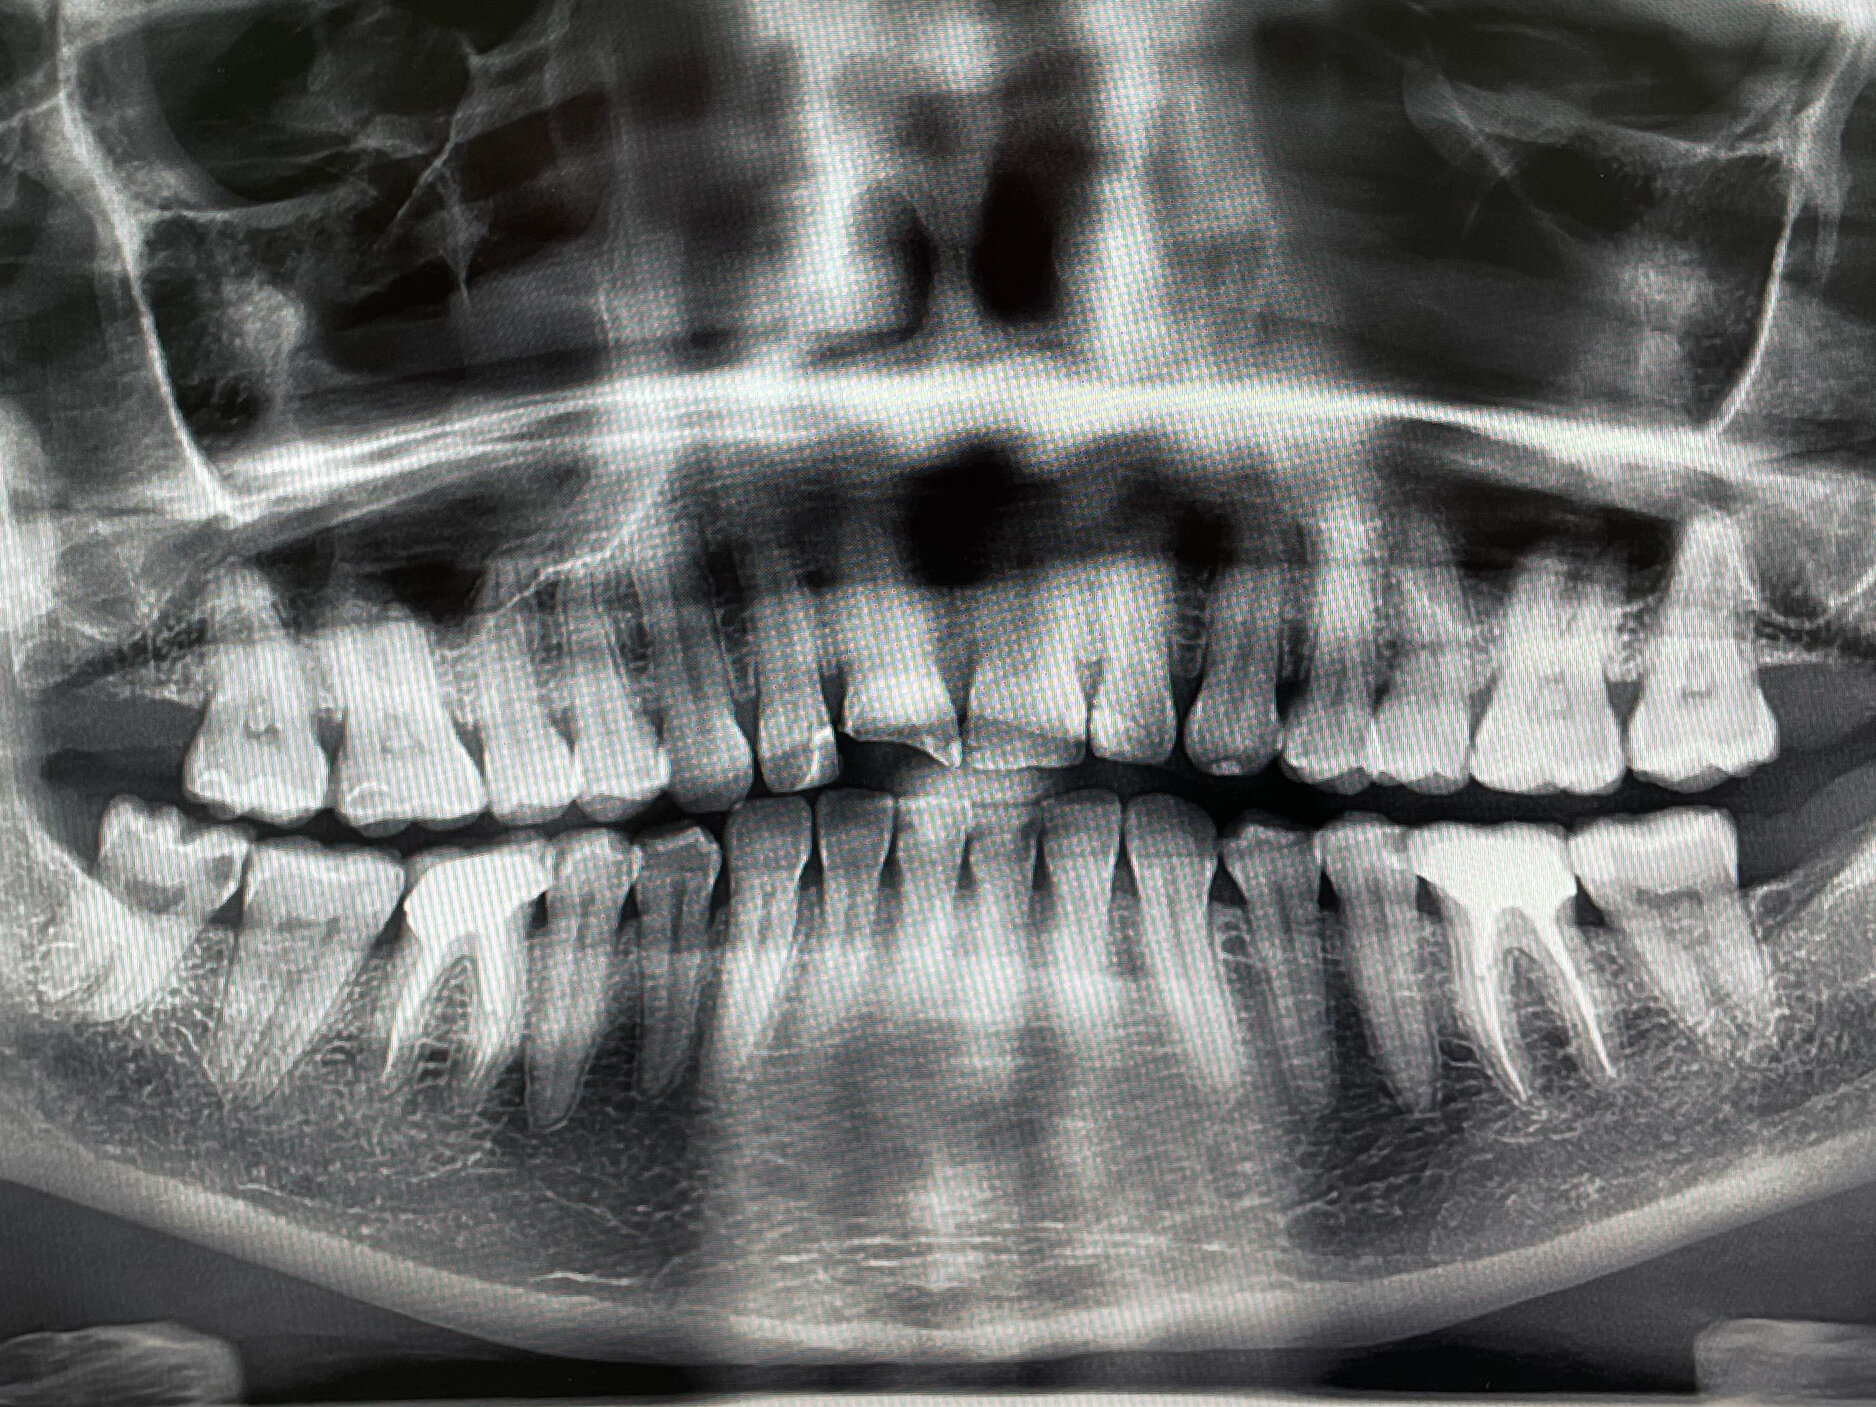

Стоматологические Исследования: Рентген Инвагинации Зубов